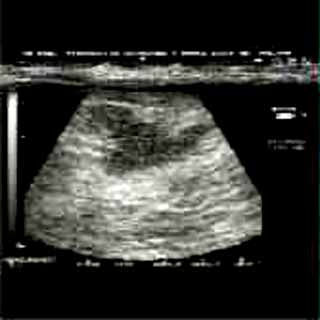

Η κλινικο-υπερηχογραφική διερεύνηση του μαστού είναι μία ακίνδυνη και πολύ αποτελεσματική μέθοδος εντόπισης εστιακών ευρημάτων.

Οι απεικονίσεις των περιστατικών που επιδεικνύονται παρακάτω, έγιναν με κυρτές κεφαλές 3,5 και 5 ΜΗΖ, προκειμένου να φανεί, ότι και με τον εξοπλισμό αυτό, που σιγά-σιγά διαθέτουν όλο και περισσότερα ιατρεία, είμαστε σε θέση να έχουμε ικανοποιητικά αποτελέσματα.

Oι τελευταίες 4 απεικονίσεις έγιναν με ειδικό για μαστό ηχοβολέα linear, εναλλασσομένης συχνότητος 7,5-10ΜΗΖ.